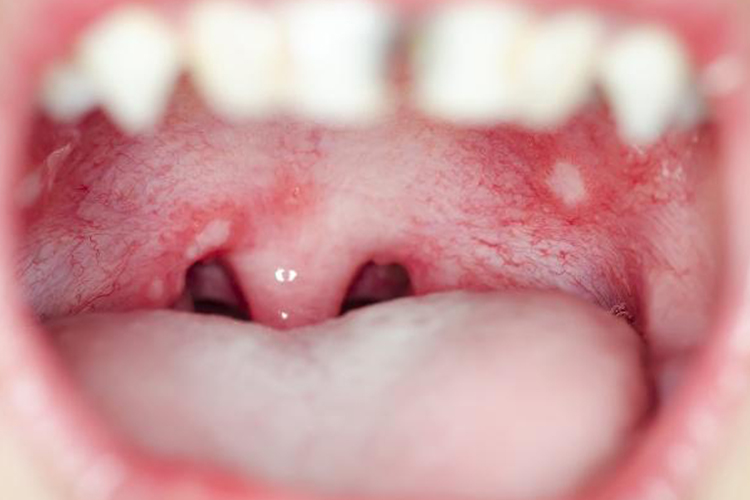

口腔后壁发炎表现为口腔后壁黏膜可出现疱疹、溃疡,损伤处黏膜红肿,可伴有疼痛症状。

口腔后壁发炎临床常见于鹅口疮、疱疹性口腔炎、溃疡性口腔炎等疾病导致。

鹅口疮:口腔后壁黏膜表面覆盖白色乳凝块样小点或小片状物,可逐渐融合成大片,不易擦去,强行剥离后局部黏膜潮红、粗糙,可有溢血。通常不伴有疼痛,不影响进食,鹅口疮严重时可出现低热、吞咽困难等症状。

疱疹性口腔炎:起病时发热可达38-40℃,1-2天后口腔后壁黏膜出现单个或成簇的小疱疹,直径约2mm,周围有红晕、红肿发炎表现,疱疹迅速破溃后形成溃疡,有黄白色纤维素性分泌物覆盖,多个溃疡可融合成不规则的大溃疡,有时累及软腭、舌和咽部。由于疼痛剧烈,患者可表现拒食、流涎、烦躁。体温在3-5天后恢复正常,病程约1-2周。

溃疡性口腔炎:口腔后壁可见充血、水肿,出现疱疹后发生大、小糜烂或溃疡,创面覆盖较厚的纤维素性渗出物,形成白色或黄色的假膜。局部疼痛,淋巴结肿大、拒食。发热,体温达39-40℃。